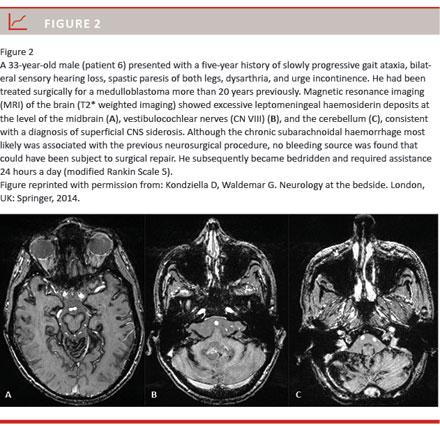

In the “classic” or “infratentorial” type of superficial CNS siderosis, subpial haemosiderin deposits of the brain and spinal cord accumulate due to chronic subarachnoid haemorrhage, often causing progressive ataxia, deafness, dementia and sometimes a bed-ridden helpless state (Figure 1 and Figure 2) [1-9]. Many different conditions can lead to this form of superficial CNS siderosis, including congenital malformations such as fluid-filled collections in the spinal canal, CNS tumours, post-neurosurgery, head or back trauma, arteriovenous malformations and brachial plexus/root injuries [4, 5]. Surgical removal of the bleeding source remains the only causative treatment option. However, knowledge about treatment outcomes is scarce and typically derived from single case reports [1, 3, 5-9]. We therefore present a consecutive case series from a tertiary neuroscience centre in order to stress the challenges related to diagnosing and treating patients with superficial CNS siderosis.